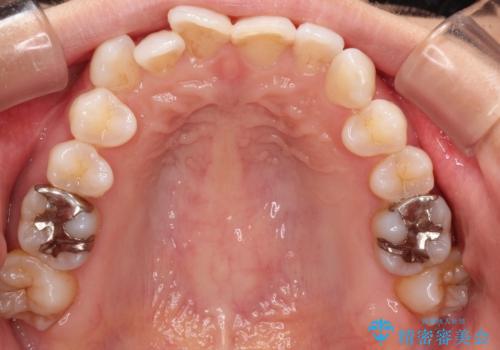

八重歯と前歯のガタガタをインビザラインで

- 八重歯と前歯のガタガタを主訴に来院されました。

目立たず矯正したいとのことでインビザラインで矯正することとしました。

インビザラインで目立たずに治療を終えることができ、喜んでいただけました。